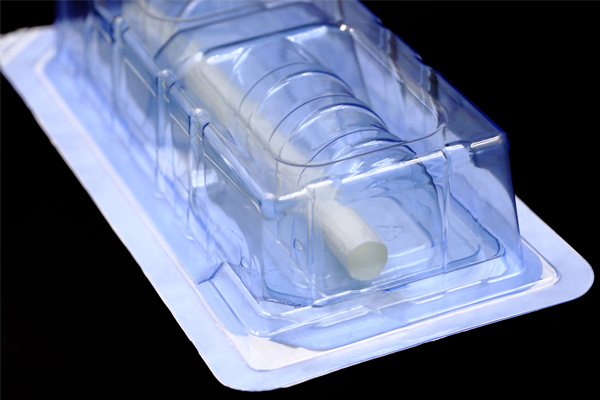

jinnian金年会成立于2009年4月,是集团旗下专业从事高端医疗器械研发、生产与销售的国家高新技术企业,坐落于国家级生物产业基地-武汉光谷生物城。现拥有1000m²符合GMP要求的万级洁净厂房;授权和受理国内外发明专利近20项;2017、2018年连续两年承担国家重点研发计划项目。